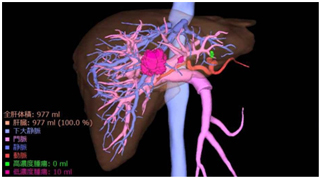

マルチスライスCT装置は、短時間で広範囲を撮影することができ、息を止めていただく時間が短いため、患者さんにとってより優しい検査が行えます。また、データ量が多く、高精細な3D画像、血管像、任意の断面像を作ることができます。

2管球CTでは、46cmの長さを1秒で撮影できる速さを持ち、息止めの困難な患者さんや、動きの速い心臓の撮影にとても強い装置です。また、低管電圧を活用して放射線被ばくを減らし、造影剤の使用量も抑えて検査することが可能となりました。

肝臓血管3D画像